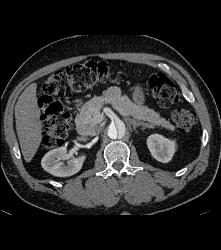

Peripheral Vascular Disease (PVD) - Left More Than Right